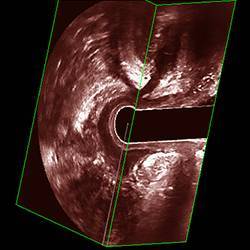

西安马应龙肛肠医院丹麦BK腔内超声

患者取合适体位后 , 暴露臀部与肛门 , 检查者戴手套先行肛门指诊 , 初步了解病变部位与范围 , 再将涂有耦合剂的直肠腔内超声探头插入肛门 , 嘱患者张口呼吸 , 并放松肛门 。 探头方向略前倾 , 通过肛管后将探头后倾 , 到达直肠壶腹部后再次前倾 , 如使用双平面探头应依检查需要交替使用线阵模式与凸阵模式 。